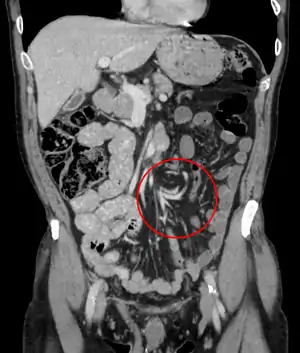

| Coronal CT of the abdomen, demonstrating a volvulus as indicated by twisting of the bowel stock | |

CT scan of a small bowel volvulus. It shows two juxtaposed segments of narrowing, which is the spot of mesentery rotation. The other signs indicate strangulation.